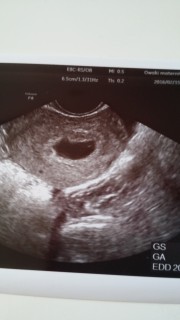

三人目の妊娠! 生理がおくれて約1週間後に受診。五週目くらいですと言われました! 三人目ですが毎度毎度ちゃんと育ってくれてるのか心配で次の2週間後の検診が待ち遠しい~(;o;)笑

初めての妊娠でドキドキでしたが、正常妊娠でひと安心☆胎嚢は9.9ミリでした♪

4w3dで初診に行ったのですが胎嚢 確認できず一週間後の今日確認できました

先生から「妊娠してますね、正常妊娠ですよ」と言われて一安心でした。まだまだ小さいですけど、とっても愛おしい初めてのベビーたちゃんです。